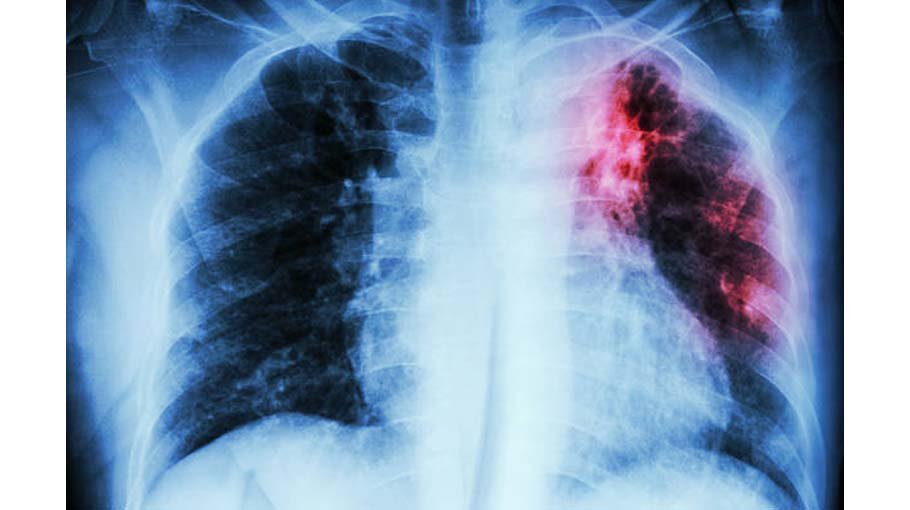

Pulmonary fibrosis is a lung disease that occurs when lung tissue becomes damaged and scarred. This thickened, stiff tissue makes it more difficult for your lungs to work properly. As pulmonary fibrosis worsens, you become progressively more short of breath.The scarring associated with pulmonary fib...

• Thortness of breath (dyspnea)• A dry cough• Fatigue• Unexplained weight loss• Aching muscles and joints• Widening and rounding of the tips of the fingers or toes (clubbing)The course of pulmonary fibrosis — and the severity of symptoms — can vary considera...

The lung scarring that occurs in pulmonary fibrosis can't be reversed, and no current treatment has proved effective in stopping progression of the disease.Medications:Your doctor may recommend newer medications, including pirfenidone (Esbriet) and nintedanib (Ofev). These medications may help s...

High blood pressure in your lungs (pulmonary hypertension): Unlike systemic high blood pressure, this condition affects only the arteries in your lungs. It begins when the smallest arteries and capillaries are compressed by scar tissue, causing increased resistance to blood flow in your lungs. This ...